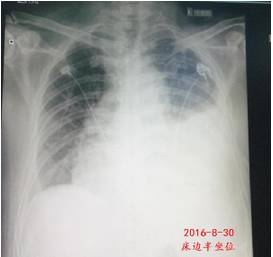

第二天复查胸片如下。

2016-9-1进一步行胸部CT平扫+增强:双侧少量胸腔积液(左侧略多),左下肺局部肺不张,左肺炎症。双上肺少许纤维硬结钙化灶,双上胸膜局部增厚、粘连。